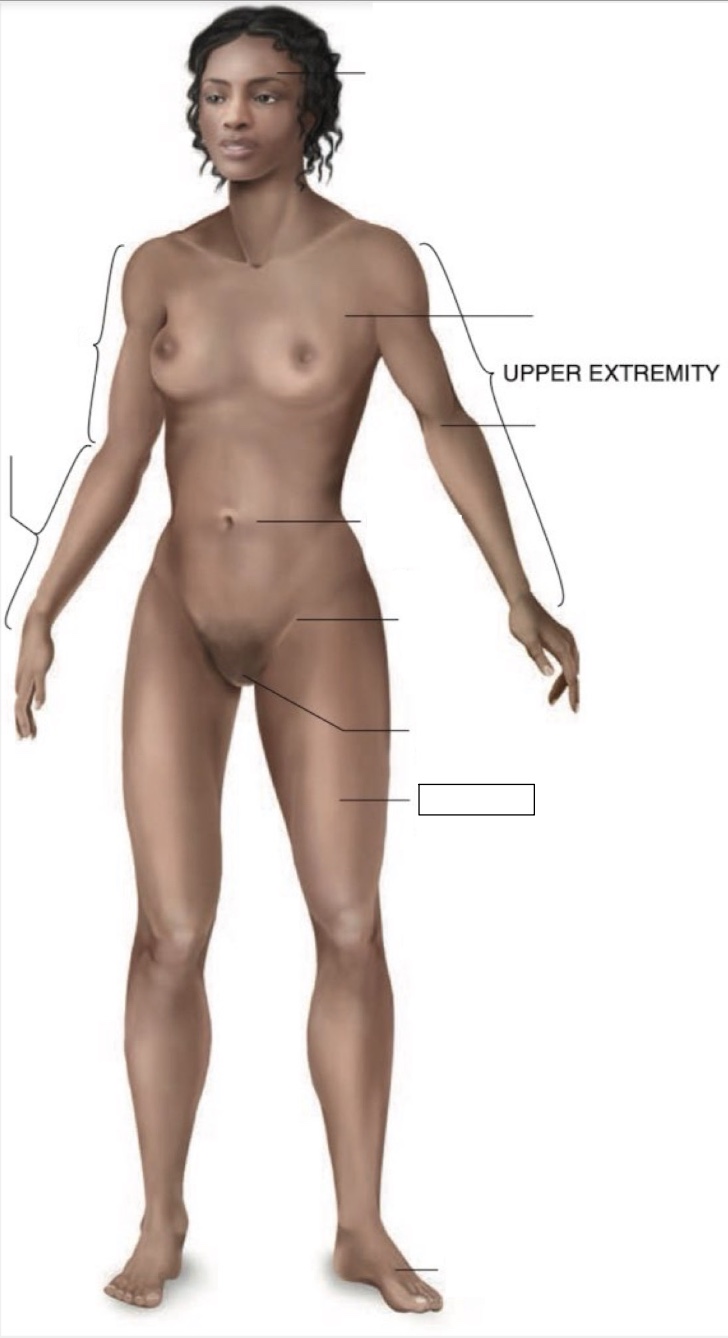

femoral region